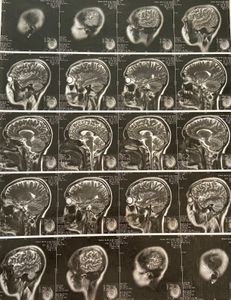

Olá! Meu nome é Bianca Helen Tiburcio, tenho 23 anos e estou enfrentando a luta contra um tumor cerebral localizado no tronco encefálico. Desde março estou afastada do trabalho e, junto com meu marido, vivemos uma batalha diária para lidar com os desafios do tratamento.

O exame de imunoistoquímica, realizado após a biópsia, trouxe resultado inconclusivo devido à escassez de material. Já está confirmado que se trata de um câncer cerebral, mas ainda não foi possível identificar com 100% de certeza o tipo específico. Existe a suspeita de glioma, pela localização, mas a definição final caberá ao especialista do hospital de referência para o qual aguardo vaga (UNESP, Hospital Amaral Carvalho ou Hospital de Amor – Barretos).

Muitas pessoas perguntam por que não realizo uma nova biópsia. Infelizmente, isso é impossível: durante a primeira biópsia sofri uma hemorragia subaracnóidea e quase fiquei com sequelas irreversíveis. Uma nova coleta de material seria de risco extremo, já que a região do tumor é extremamente sensível e próxima a funções vitais do corpo. Por isso, os médicos descartaram totalmente essa possibilidade.